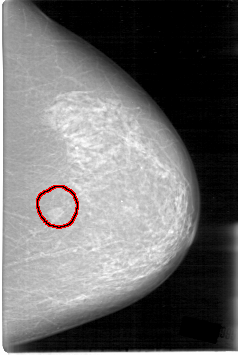

D_4014_1.LEFT_CC

LEFT_CC LINES 5311 PIXELS_PER_LINE 3556 BITS_PER_PIXEL 12 RESOLUTION 43.5 OVERLAY

FILE: D_4014_1.LEFT_CC.OVERLAY

TOTAL_ABNORMALITIES 1

ABNORMALITY 1

LESION_TYPE MASS SHAPE LOBULATED MARGINS OBSCURED

ASSESSMENT 0

SUBTLETY 5

PATHOLOGY BENIGN

TOTAL_OUTLINES 1

BOUNDARY